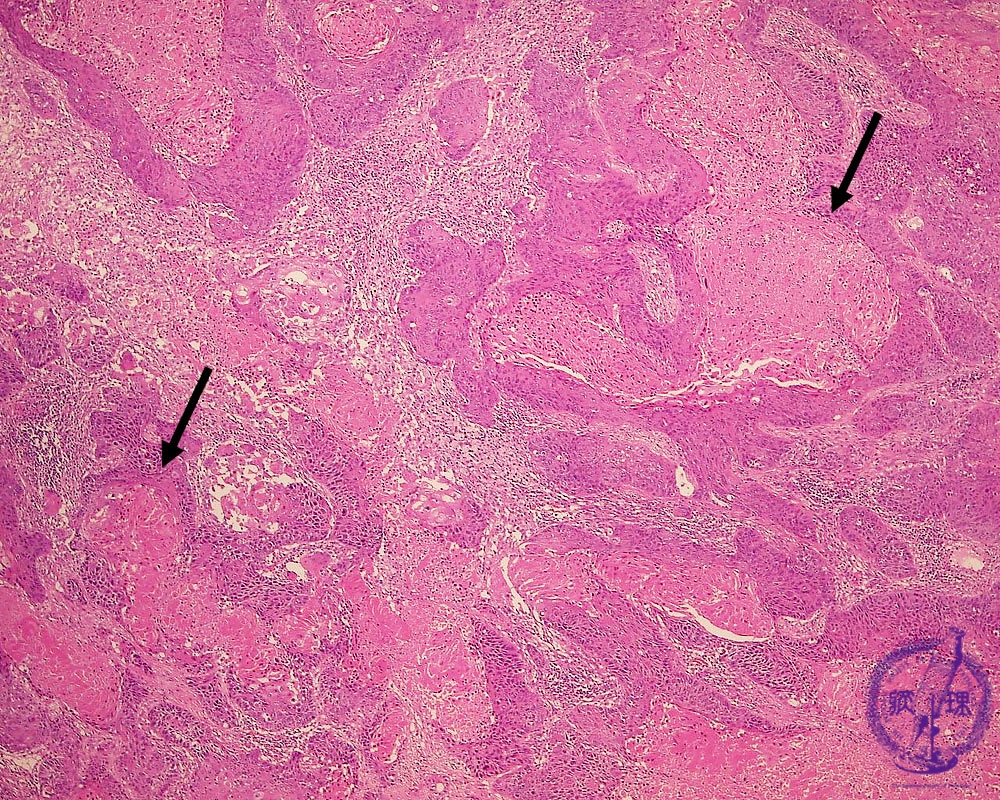

- ★(17)Non-small cell lung carcinoma(squamous cell carcinoma)

Microscopic view (HE stain, low power view): Squamous cell carcinoma proliferates in an irregular geographic (map-like) pattern. Keratinocyte necrosis is prominent (arrow). Unlike in adenocarcinoma well-formed tubules are not seen.